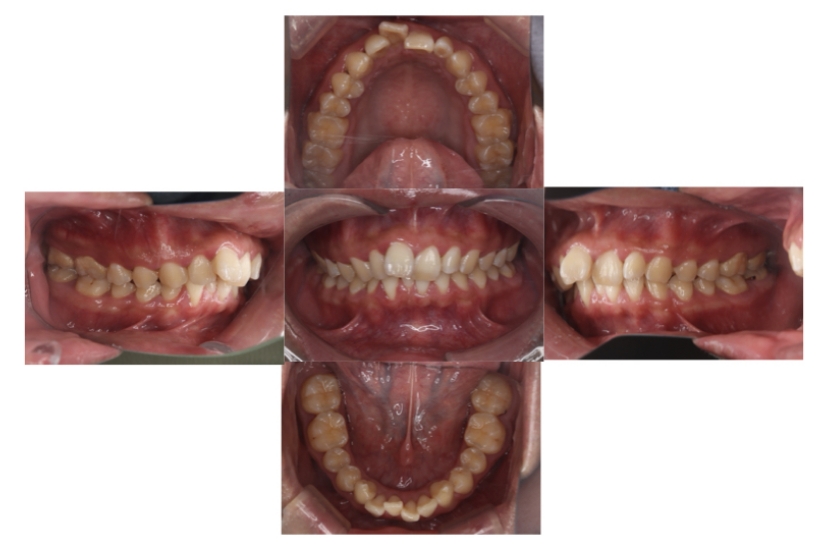

BEFORE

AFTER

上下顎前突、叢生

抜歯

ブラケット矯正

上下顎前突、叢生(上下出っ歯、上下の前歯のガタガタ)のケースです。

装置はラビアル(上下表側)で、上下顎の小臼歯を4本抜歯を行っています。抜歯したスペースを使って、上下の前歯の後方移動と叢生(ガタガタ)の改善を行っています。

主訴 前歯のガタガタと口元がでているのが気になる。

年齢・性別 30歳 女性

お住まいの地域 東京都大田区

治療方針 抜歯スペースを利用して上前歯の叢生(ガタガタ)と口元突出の改善

抜歯部位 上下顎左右第一小臼歯

使用装置 ラビアル(上下表側)、顎間ゴム

治療期間 1年11か月

治療回数 13回

リテーナー クリアリテーナー